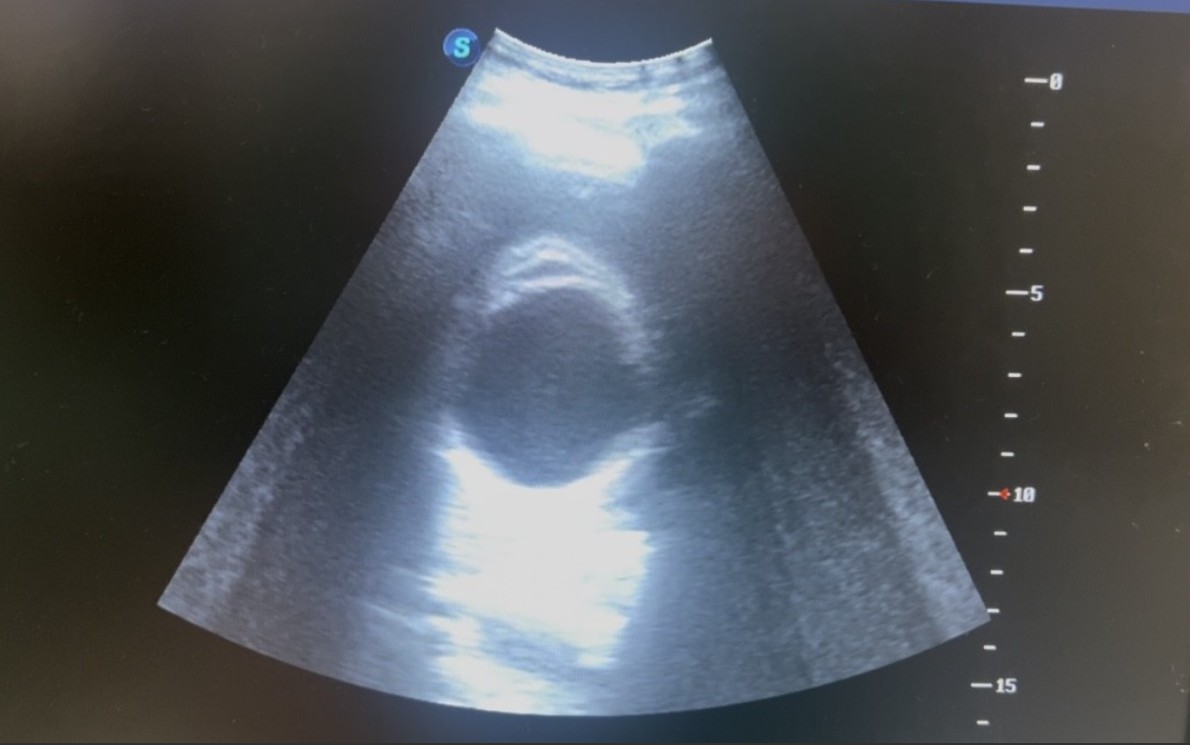

Hombre de 85 años. IABVD. Vive solo en su domicilio y cuida de un huerto. Sin antecedentes personales relevantes. NO FRCV. Traído a SUH por UVI móvil, es encontrado por su hija en su domicilio con desconexión del medio. NO responde a estímulos. A llegada de UVI móvil TA de 80/40. Difícil anamnesis porHallazgos ecográficos

Se le realiza protocolo RUSH en el que única alteración reseñable: distensión vesicular de 10 x 4 cm, con imagen de bole pared sugestiva de signo del «agujero ecográfico» asociando edema y aparente dilatación de colédoco.Pruebas complementarias